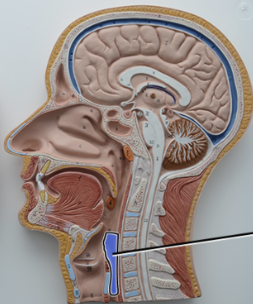

What structure is this?

Thyroid Cartilage

What structure is this?

Cricothyroid Ligament

Cricoid Cartilage

What structure is this?

Epiglottis

What structure is this?

Trachea

What structure is this?

Tracheal Cartilage